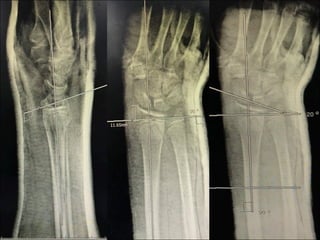

X-ray Right wrist

AP,Lateral

Impression

• Right wrist

• Close fracture

• Extra articular

• Anterior displacement

• Volar tilt

• Radial inclination 14˚

• Radial height 8mm

• Salter-Harries type 2

• Fernandez type 2